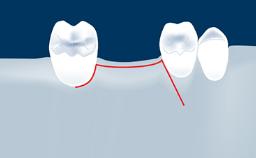

Digitally Guided Sinus Floor Elevation

In this short microlearning module on digitally guided sinus floor elevation, we delve into a specialized aspect of the digital workflow for implant-guided surgery, focusing on the use of digital guides in the sinus floor elevation technique.